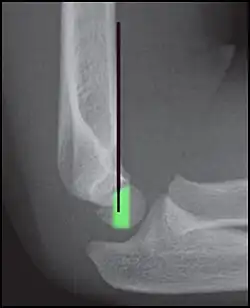

Percutaneous pinning

Percutaneous pinning are usually inserted over the medial or lateral sides of the elbow under X-ray image intensifier guidance. There is 1.8 times higher risk of getting nerve injury when inserting both medial and lateral pins compared to lateral pin insertion alone. However, medial and lateral pins insertions are able to stabilise the fractures more properly than lateral pins alone. Therefore, medial and lateral pins insertion should be done with care to prevent nerve injuries around elbow region.[3]

Percutaneous pinning should be done when close manipulation fails to achieve the reduction, unstable fracture after closed reduction, neurological deficits occurs during or after the manipulation of fracture, and surgical exploration is required to determine the integrity of the blood vessels and nerves. In open fractures, surgical wound debridement should be performed to prevent any infection into the elbow joint. All Type II and III fractures requiring elbow flexion of more than 90° to maintain the reduction needs to be fixed by percutaneous pinning. All Type IV fractures of supracondylar humerus are unstable; therefore, requires percutaneous pinning. Besides, any polytrauma with multiple fractures of the same side requiring surgical intervention is another indication for percutaneous pinning.[3]